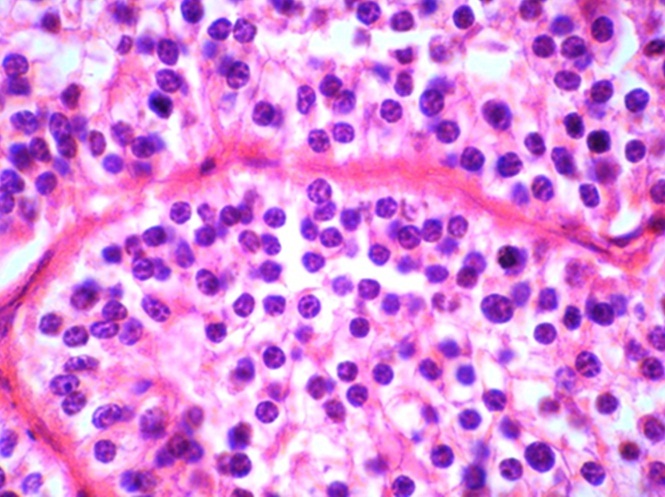

The patient was referred to the surgical department. A left side thyroid lobectomy was performed. On macroscopic examination the left lobe was 5x2.5x2 cm. A 3-cm, creamy-whitish solid nodule, confined to thyroid capsule, was identified [Table/Fig-1]. Microscopically, the lesion was consisted of uniform cells with light eosinophilic cytoplasm encompassing round, monomorph nuclei with punctate chromatin and fine nucleoli, arranged in diffuse and trabecular pattern with a well-developed capillary network [Table/Fig-2]. After operation, the patient complained of muscular spasm in the legs and numbness and tingling in the fingertips. Calcium level was 7.7 mg/dl postoperatively. Follow-up of the patient revealed slow rise in calcium levels and relief of symptoms. This could be in favor of parathyroid adenoma and can be explained by atrophy of residual glands in the presence of a single hyperfunctioning adenoma. Unfortunately we did not have any information about the patient’s preoperative calcium level. The differential diagnoses were: parathyroid adenoma, follicular adenoma of thyroid and medullary carcinoma of thyroid. For definite diagnosis, immunohistochemical study of the lesion with three markers was done. TTF-1 was negative so follicular lesion of thyroid was ruled out [Table/Fig-3]. Calcitonin was also negative so there was no possibility of medullary carcinoma [Table/Fig-4]. PTH marker was positive in cytoplasms of cells [Table/Fig-5] and parathyroid adenoma was confirmed.

Trabecular pattern with a well-developed capillary network.